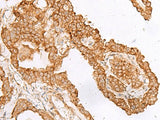

FAM200A Polyclonal Antibody

Reactivity Human

Applications IHC

IHC 1:40-1:200